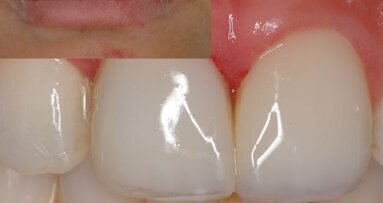

El autor describe los procedimientos clínicos y terapéuticos para la rehabilitación de dientes anteriores fracturados con fractura ...